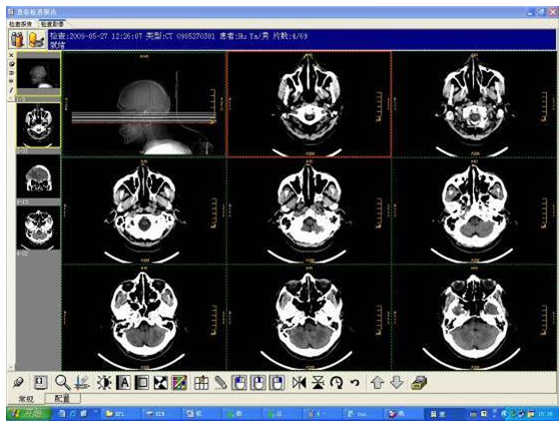

全院级医学影像管理平台(PACS)

亚创PACS率先实现将医院所有检查设备集成至PACS系统之中,包括放射检查设备、超声检查设备、内窥镜、核医学检查设备、心电图等,为医院PACS系统的未来扩展打下坚实基础。针对不同类型的检查设备,采用不同的集成技术。以标准DICOM接口为主,同时采用非标准数字接口技术、通用网络虚拟输出技术等,实现将不同类型的检查设备真正统一集成至PACS并发布到临床科室实现共享,且对于硬件设备没有特定的要求。